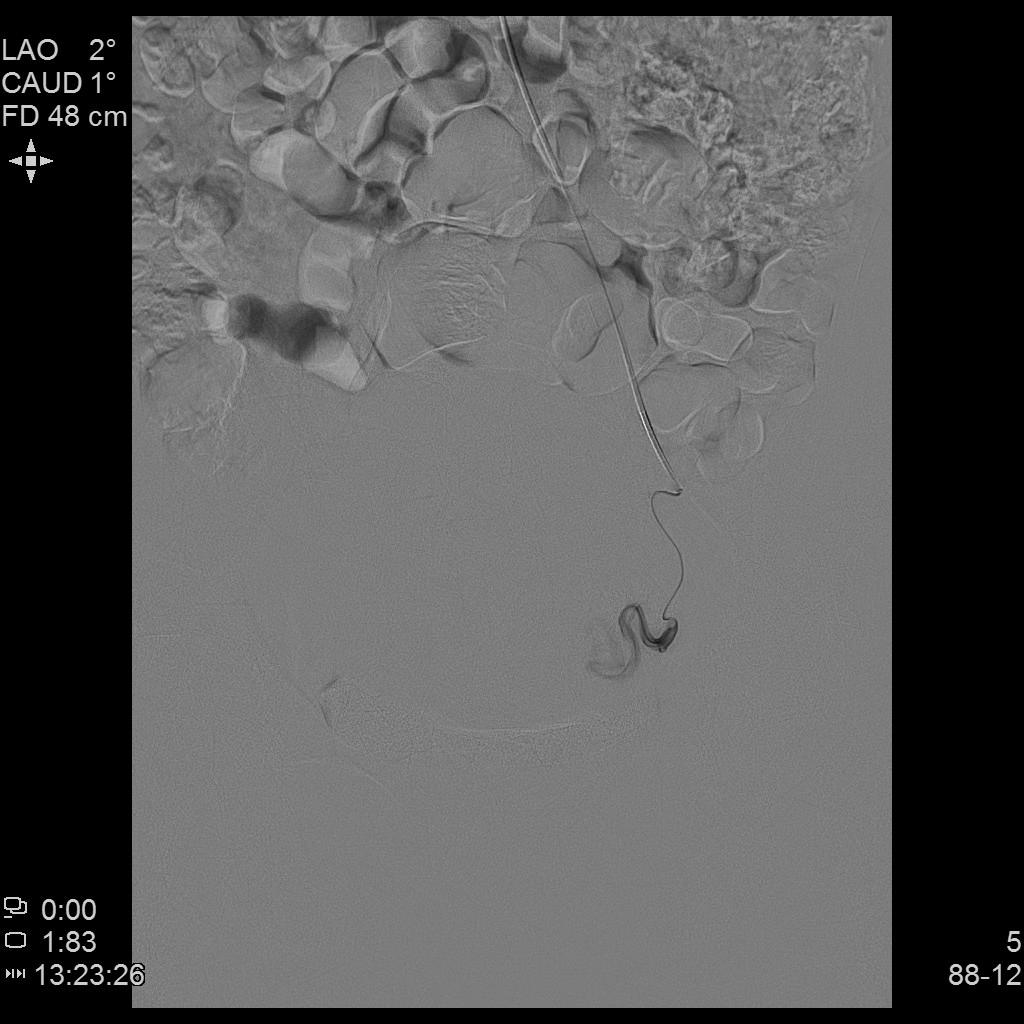

青年女性患者,痛经近10年,近5年痛经明显加重。确诊为子宫腺肌症(弥漫型),经放置曼月乐、注射亮丙瑞林等妇科保守治疗,症状缓解不理想,痛经进行性加重,严重困扰工作与生活。

• 行子宫腺肌症介入栓塞治疗

• 插管至右侧髂内动脉造影,显示右侧子宫动脉

• 插管至右侧子宫动脉,显示子宫右侧病灶情况